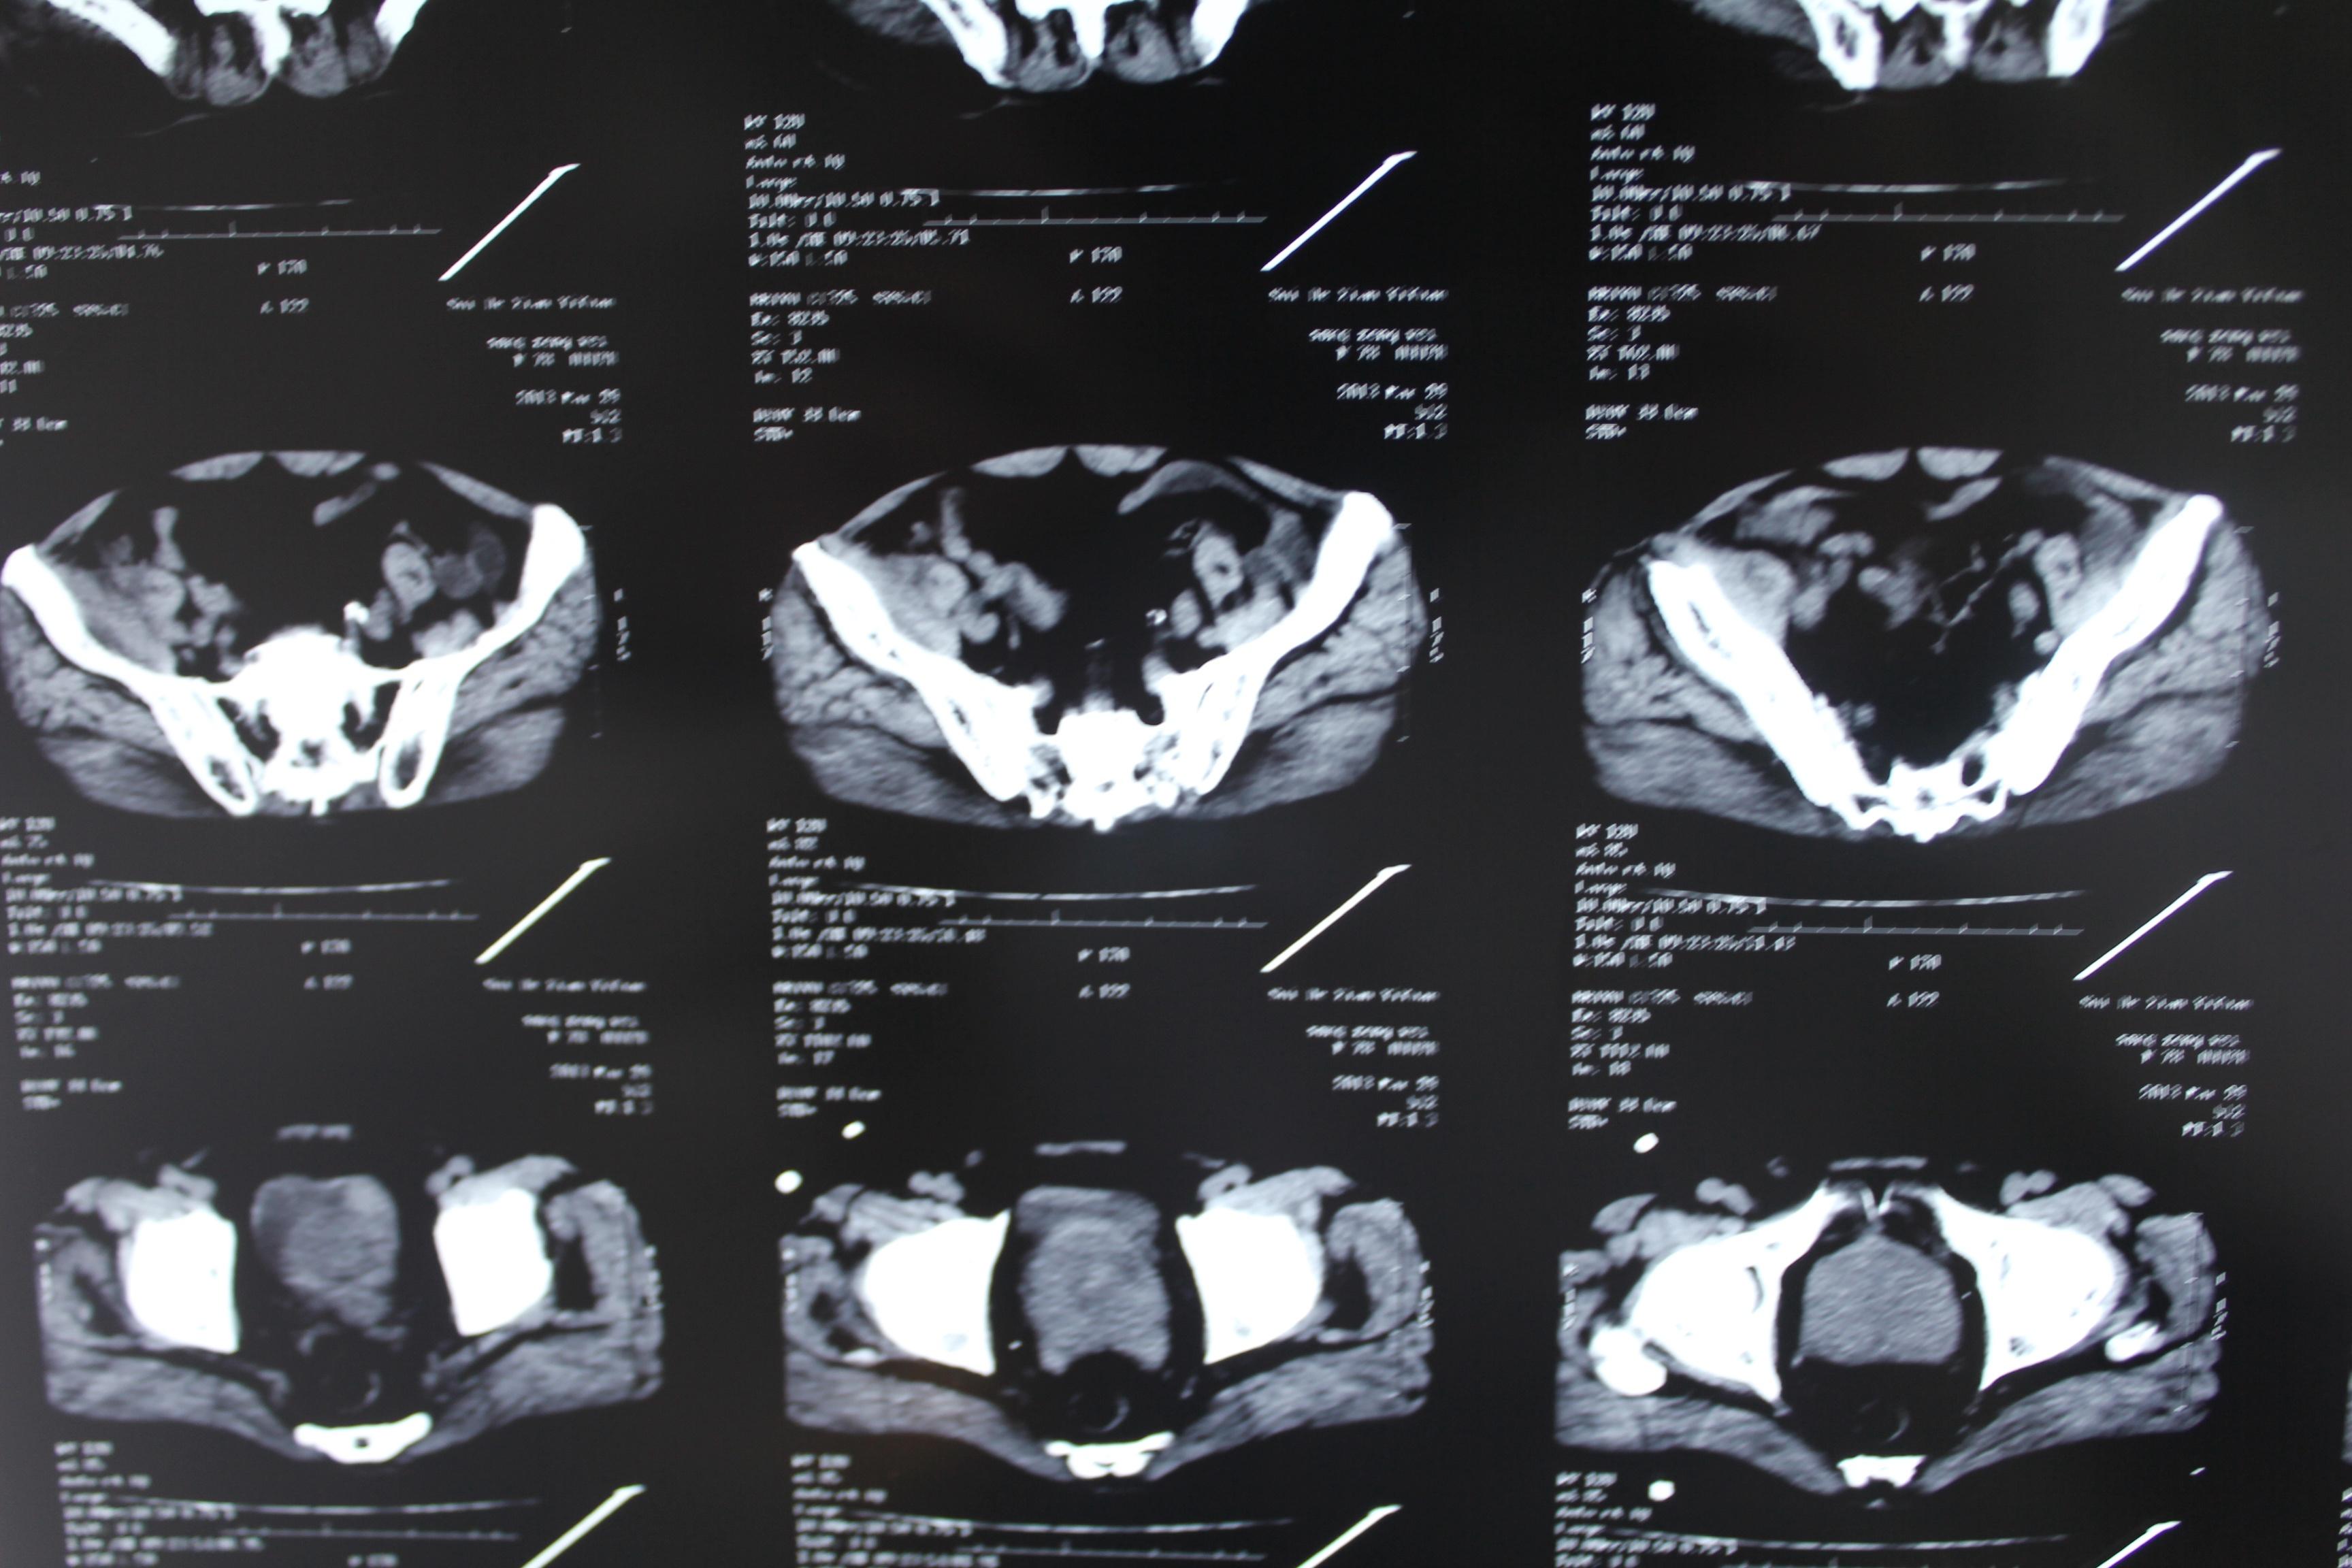

老年患者78岁,反复腰背部溃烂流脓4年,既往30年前曾在包块处排出蛔虫一条。CT:

明日手术探查